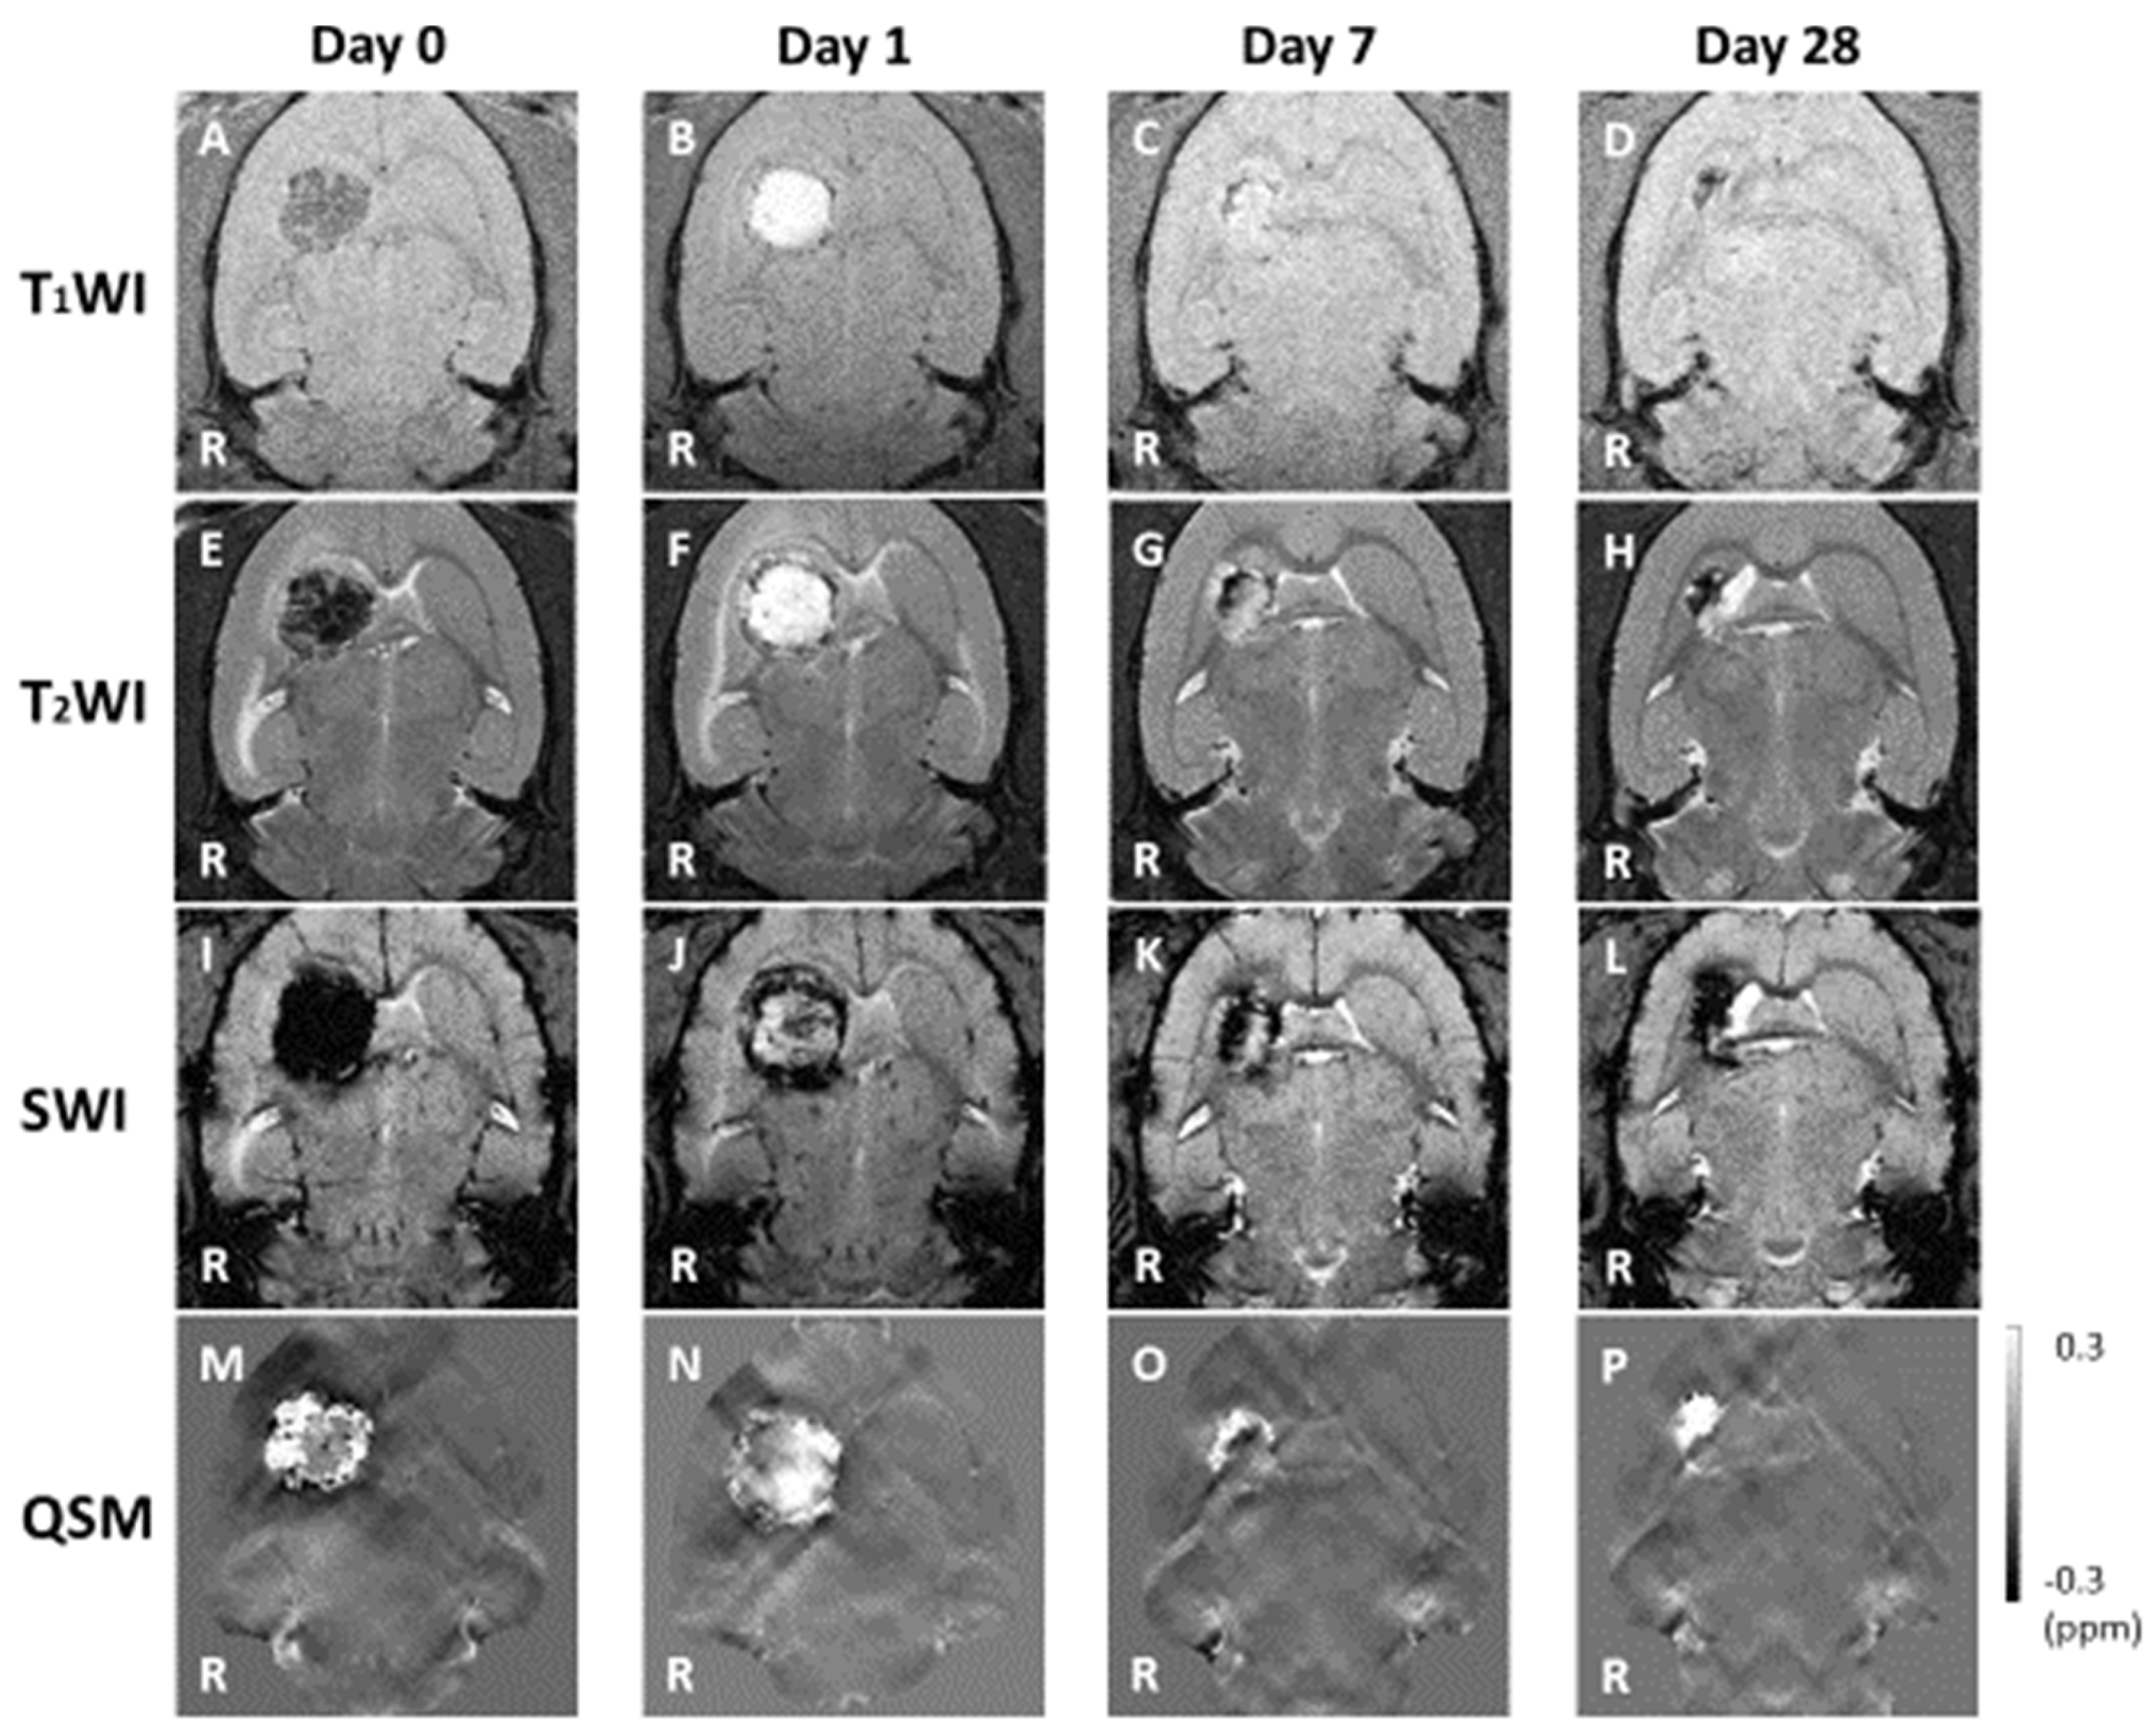

3.1. MRI Observation

3.2. Hemorrhage Signal

3.3. Hemorrhage Area

4.2. Contrast Mechanism of Bleeding

4.3. ICH Area